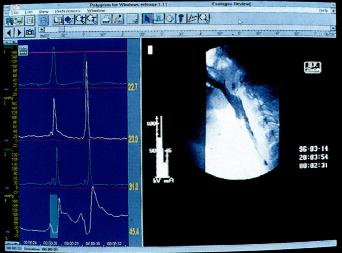

同步吞钡透视及测压检查(图2.5)

为评价吞咽异常可同步进行咽部测压及X线透视。钡透视显影与生理指标记录同步进行,检测同步显示,并以数字方式记录在同一计算机上。

图2.5同步钡透及测压检查(图取自Medtronic GastroIntestinal).

X线电视诊断